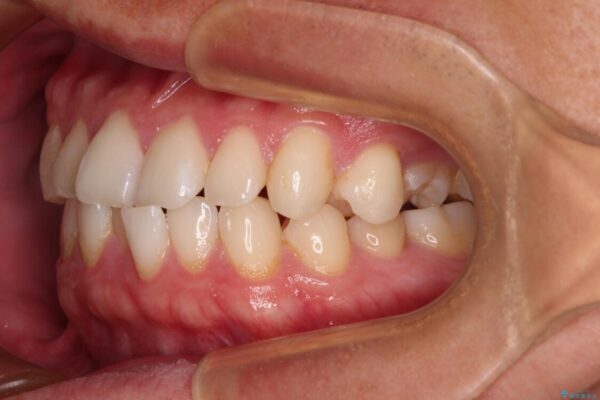

**前歯のデコボコ(叢生)**が整い、歯列全体が美しく改善

シザーズバイトの奥歯も正常なかみ合わせに改善

捻転歯も回転が修正され、全体的に清掃性・咀嚼効率が向上

患者様にも「大人になってから矯正を始めることに不安もありましたが、思っていたよりも短期間で治療が終わって本当にうれしいです。前歯のガタガタも気にならなくなり、笑うことに自信が持てるようになりました!」と喜んでいただけました。

治療後

• 前歯のガタガタ・奥歯のかみ合わせ(シザーズバイト)を改善|1年半で完了したメタルブラケット矯正 治療後画像